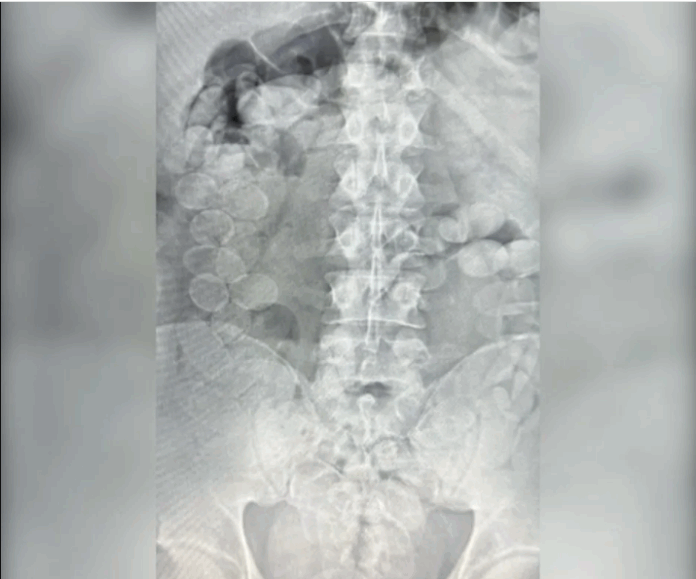

El hallazgo se produjo gracias a un perro detector de drogas que marcó a los sospechosos durante el operativo vial. Tras ser trasladados al hospital local y sometidos a estudios médicos, se confirmó que llevaban la droga en sus organismos. En total, los ahora condenados expulsaron 185 envoltorios con cocaína de alta pureza, cantidad suficiente para producir más de 20 mil dosis.